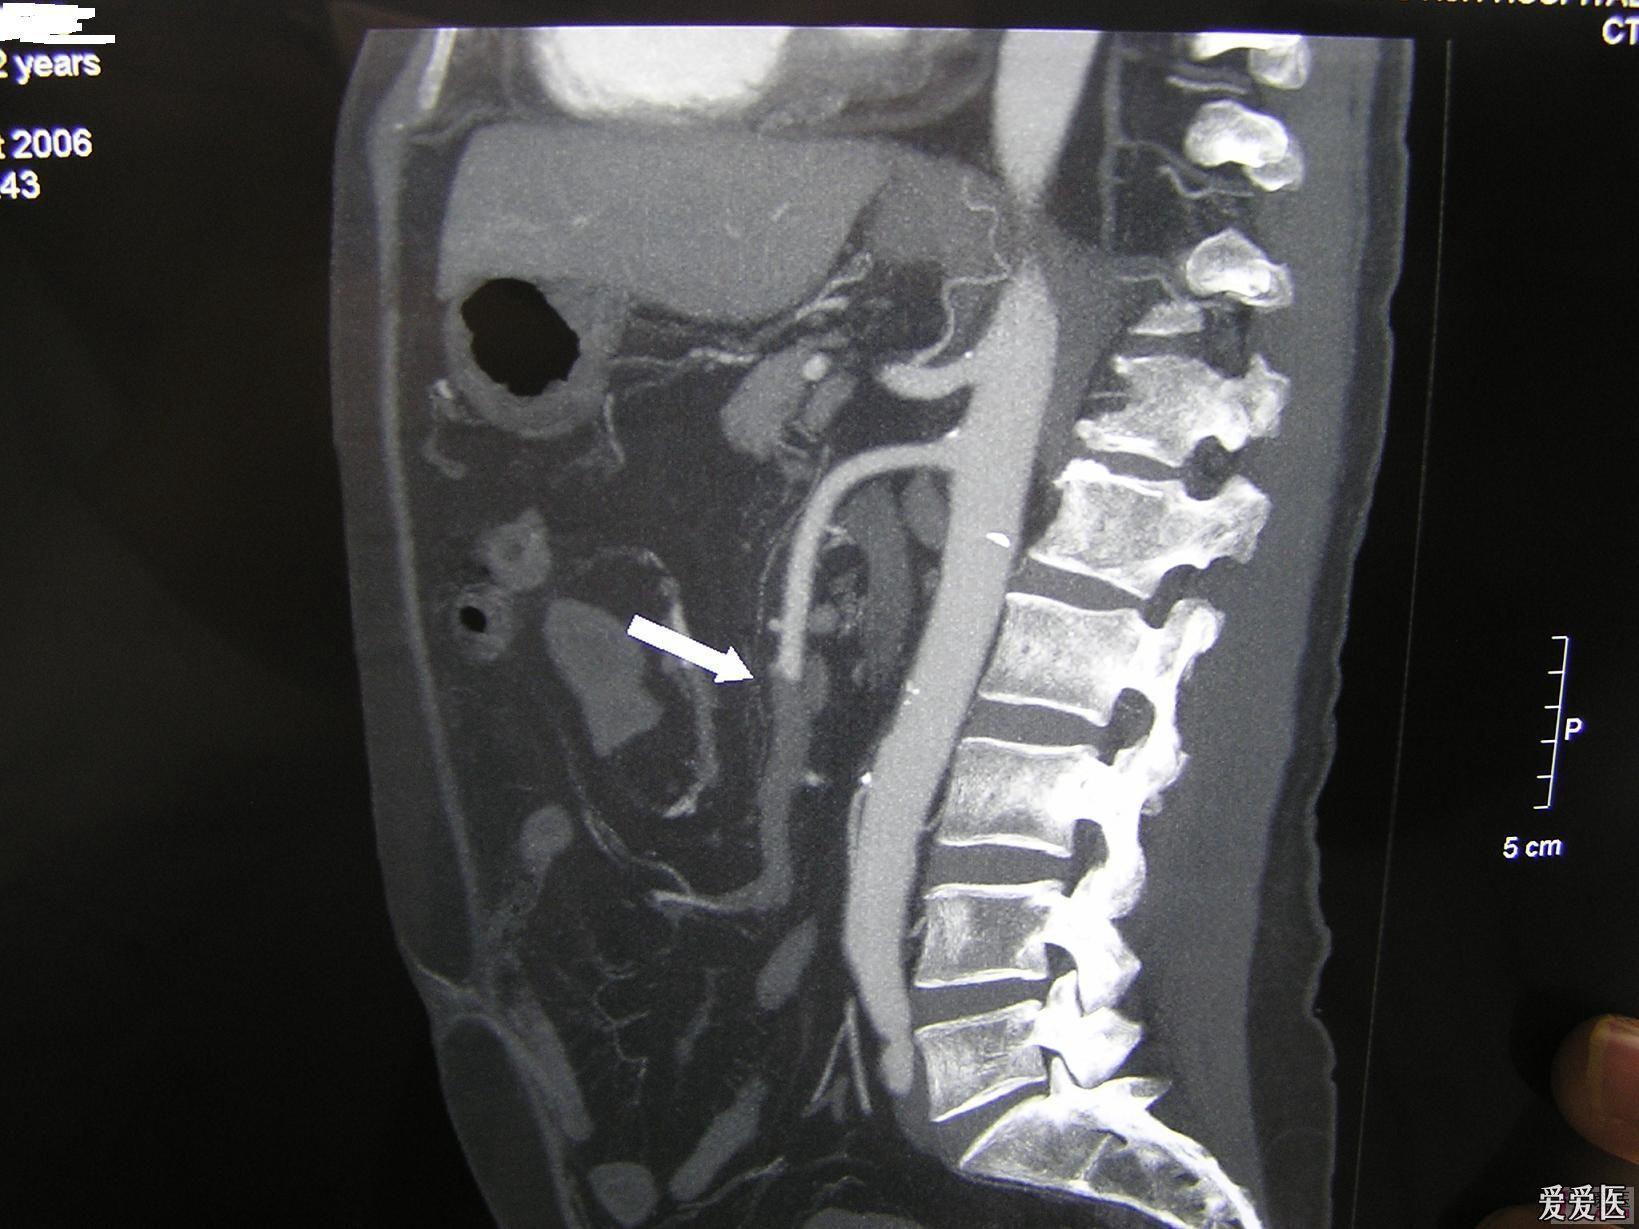

急腹症肠系膜上动脉栓塞smae误诊分析请进

图片尺寸1639x1229